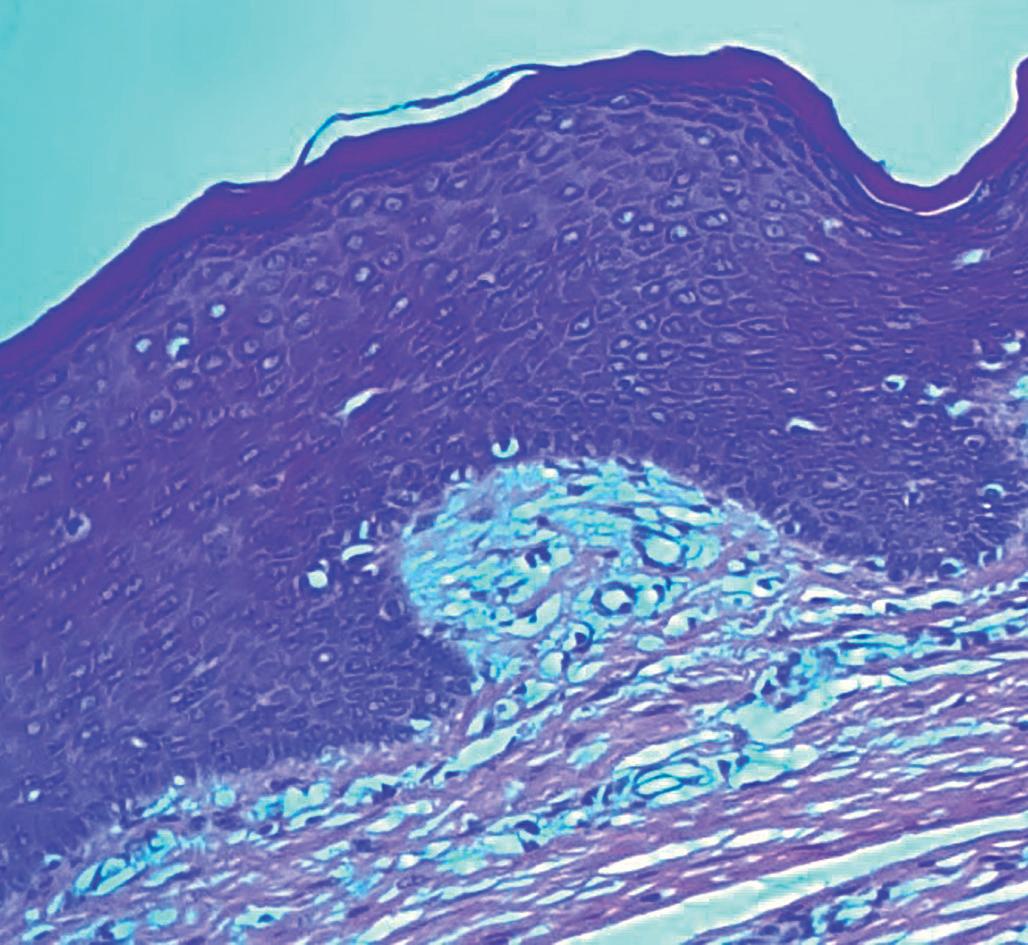

1-5. Pequeno lábio. Pele com epiderme constituída por epitélio escamoso pluriestratificado não-queratinizado sobre estroma conjuntivo. Observar a ausência de folículos pilossebáceos (HE, 10x).

o prepúcio. Os pequenos lábios são pregas finas de tecido conectivo e compostos por epitélio parcialmente queratinizado externamente e mucoso internamente, sem pelos, porém com sutis folículos pilosos (Fig. 1-5). Há glândulas sudoríparas apócrinas e sebáceas na face medial destas dobras cutâneas. As glândulas sebáceas apresentam-se como pequenas pápulas lobulares, de coloração amarela e branca que quase se confluem (Fig. 1-6). Uma linha de demarcação (linha de Hart) é evidente na base da face medial de cada pequeno lábio, separando a membrana mucosa parcialmente queratinizada da mucosa do vestíbulo (Fig. 1-7).